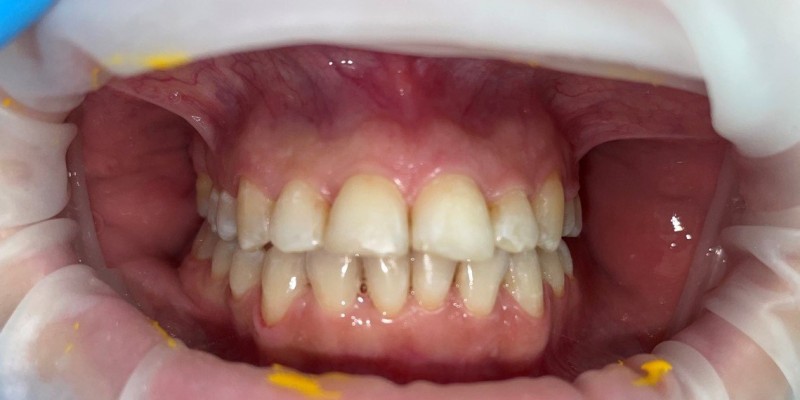

Пациентка обратилась с жалобами на сильно выраженную скученность резцов нижнего зубного ряда. Также в ходе ортодонтического лечения 6-й зуб справа на верхней челюсти ортодонтическим способом «утопили» в костную ткань, поскольку зуб вышел из окклюзионной плоскости. Тем самым значительно уменьшилось оголение шейки зуба. Продолжительность лечения 1 год, сапфировые брекеты.

Доктор: Хачатрян Лариса Рубеновна